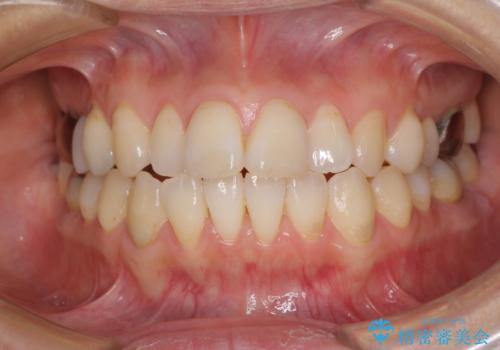

- 捻れた前歯と目立つ銀歯を気にして来院された患者様です。

歯列不正は軽微であったため、インビザライン・ライトにて改善することとしました。

インビザライン・ライトによる矯正治療であったので、時間をかけずに治療を終えることができました。

口を開ける度に目立っていた銀歯もセラミックで自然な口元の印象となりました。